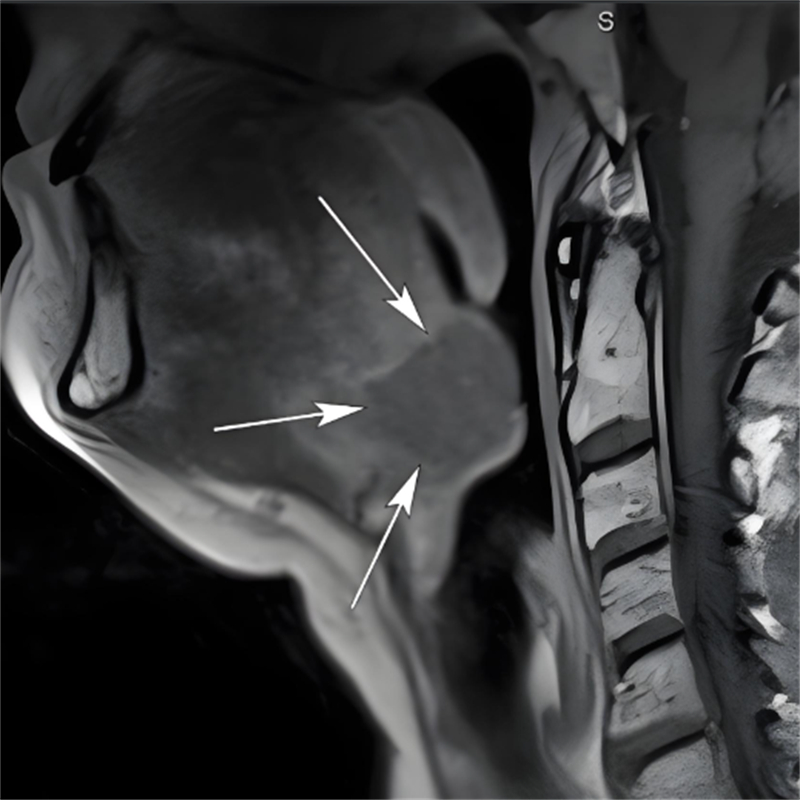

在柳州市人民醫(yī)院耳鼻咽喉-頭頸外科,接診的田芳云副主任醫(yī)師在細(xì)致查體時(shí)發(fā)現(xiàn)了關(guān)鍵線索:當(dāng)輕壓患兒舌體,舌根部竟顯露一個(gè)半球形囊性腫物。結(jié)合詳盡的病史詢問,田醫(yī)生高度懷疑患兒罹患的是“先天性舌內(nèi)型甲狀舌管囊腫(舌甲狀舌管囊腫)”。

這一診斷讓所有人都緊張起來。舌甲狀舌管囊腫,位于舌根深部,會(huì)阻塞氣道,嚴(yán)重時(shí)可導(dǎo)致患兒在睡眠中突發(fā)窒息,后果不堪設(shè)想。

醫(yī)生介紹,甲狀舌管囊腫是頸部較常見的先天性疾病,源于胚胎期甲狀舌管未完全閉鎖、上皮殘留。根據(jù)發(fā)生部位可分為“舌骨上區(qū)型、舌內(nèi)型、甲狀舌骨間隙型、胸骨上區(qū)型”四種類型,其中舌內(nèi)型(舌甲狀舌管囊腫)僅占所有病例的0.5-3%。其病灶深藏于舌根內(nèi)部,位置極其隱秘,臨床癥狀不典型,很容易被漏診或誤診。

對(duì)于低齡嬰幼兒而言,舌甲狀舌管囊腫的危害性大,是導(dǎo)致致命性上氣道梗阻的重要原因之一,甚至被確認(rèn)為嬰兒猝死綜合征(SIDS)的潛在隱匿誘因。